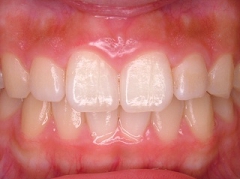

(その2)↑.

このケースは,下顎が横(右側)に大きくズレていて,上顎の歯並びに凸凹もみられます.

↑スプリント療法と,マルチブラケット矯正を併用して治療を行いました.下顎にオクルーザルスプリントを使用しながら,上顎の歯列アーチの拡大および個々の歯の整列を行った結果,下顎の右方偏位は改善し,上下の歯列の正中はほぼ一致するようになりました.